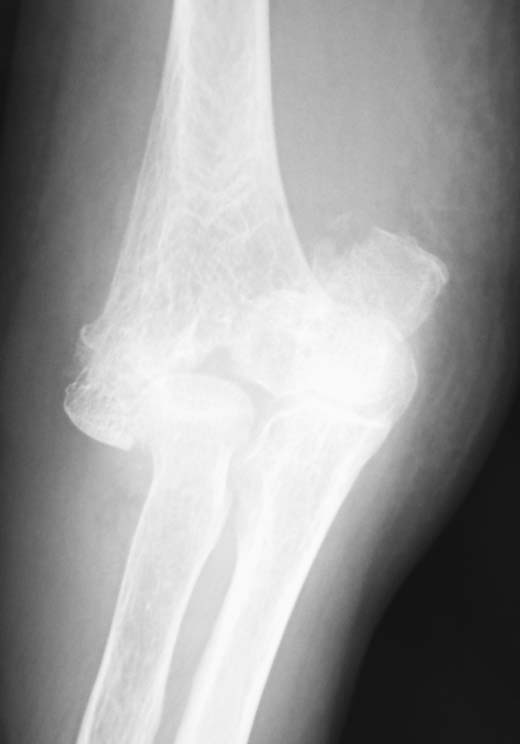

案の定、CTでは外側に骨癒合不全を認めます。前方皮質は骨癒合しているようですが、その部分より後方は内側しか骨癒合していません。

このような症例で安易に抜釘すると、術後に病的骨折を併発するリスクが高まります。この症例に限らず、ロッキングプレート使用例ではこのようなことが多い印象を受けます。